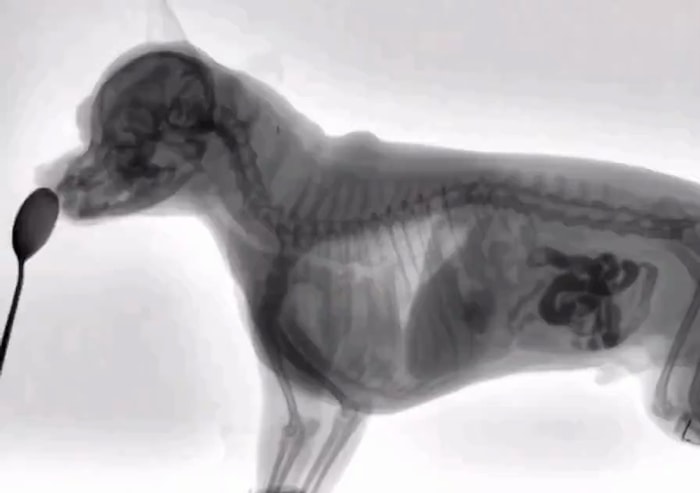

Zehirliyor: Evcil Hayvanınızı Tehlikeye Atan Ürün Açıklandı

Uzmanlar, evde yaygın olarak bulunan bir ürünün evcil hayvanlar için ciddi sağlık riski oluşturabileceğini uyarıyor. Özellikle elektronik sigara ve likitleri, farkında olmadan köpek ve kedilerin zehirlenmesine yol açabiliyor. Bu nedenle, evcil hayvan sahiplerinin bu ürünleri erişilmez yerlerde saklaması büyük önem taşıyor.